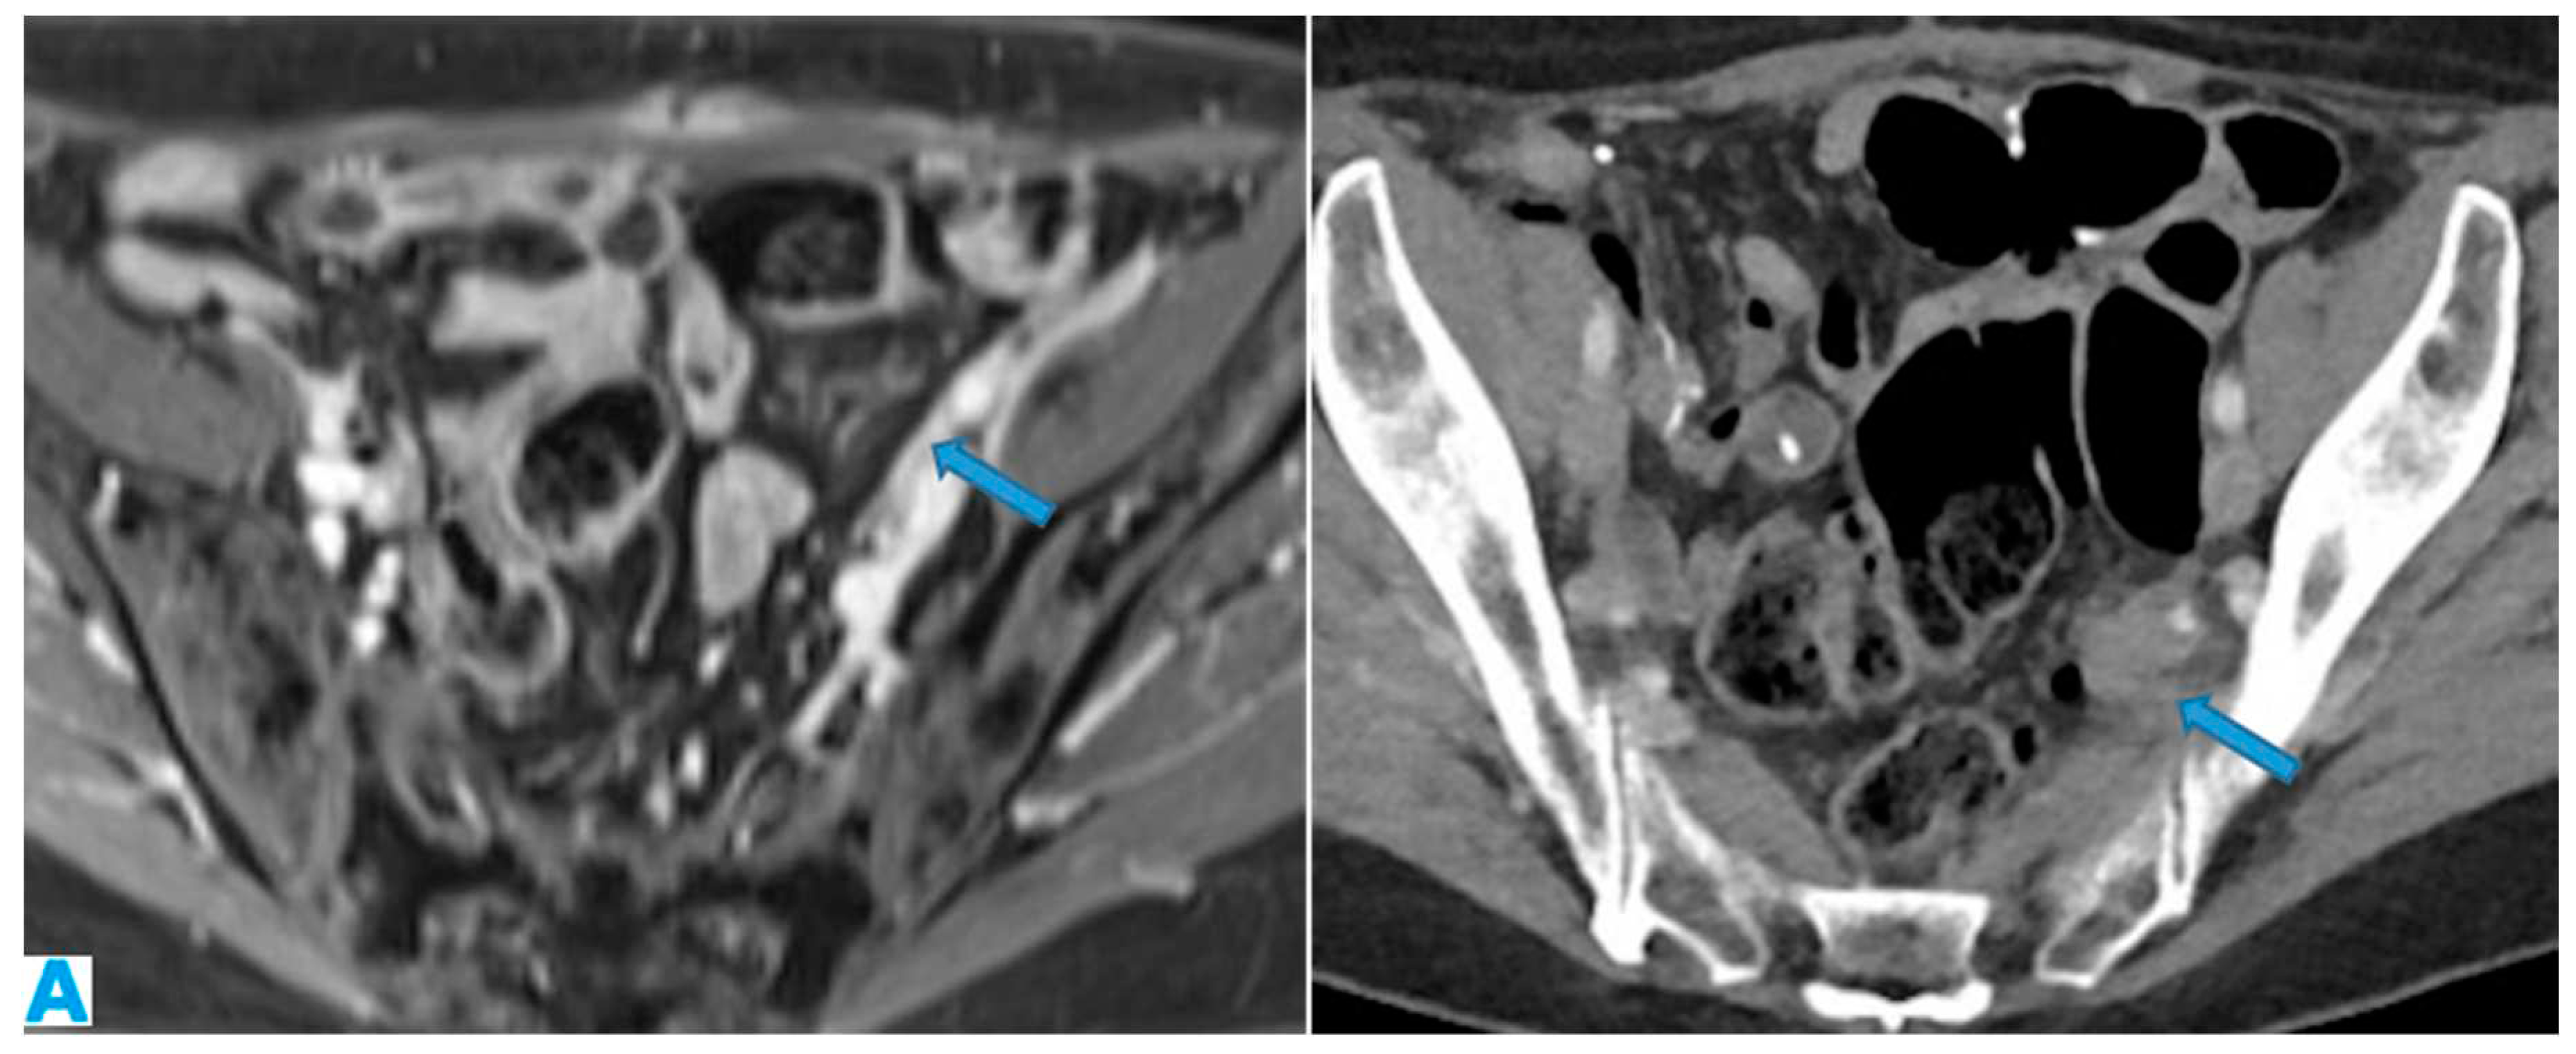

Figure 33.

Axial CE portal phase FST1WI (A). PC from duodenal adenocarcinoma: Deposit seeding within the peritoneum that covers the left pelvic wall, which looks diffusely thickened (arrow). Axial CE-CT (B). PC from undifferentiated caecal adenocarcinoma: Nodular deposit within the peritoneum that covers the left pelvic wall (arrow).